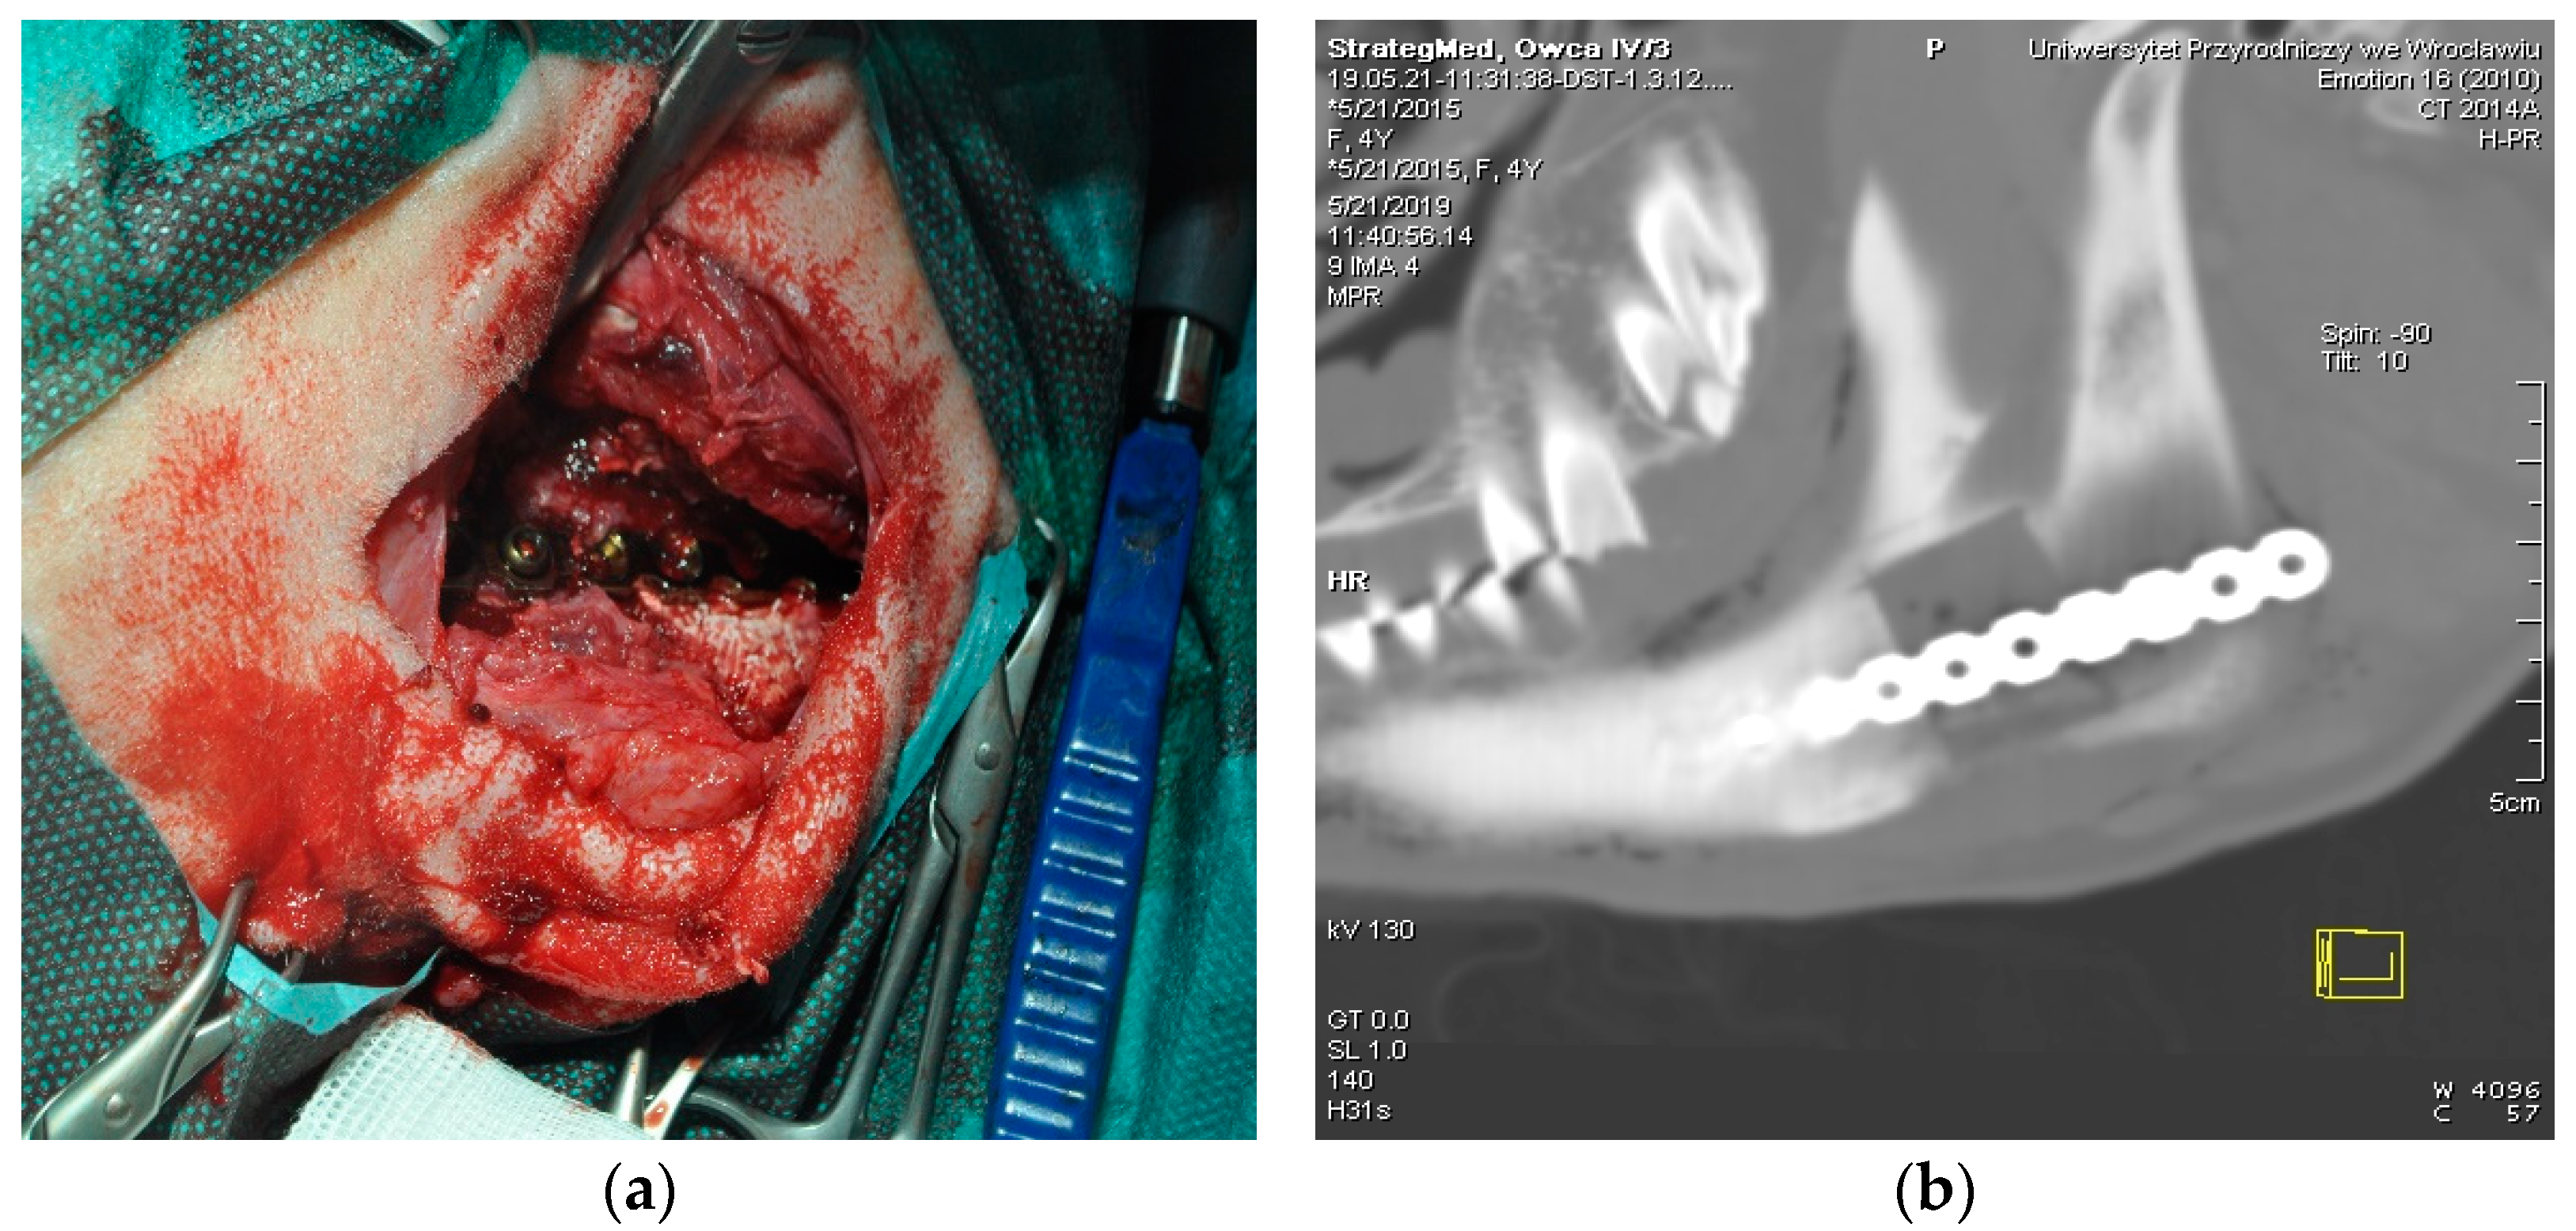

2.4. Surgical Procedure for Scaffold Implantation (SIP)

Figure 2. Procedure of scaffold implantation. (a) Surgical wound showing titanium bone plate attached with srews. (b) CT image of the scaffold placed in the ovine mandible.